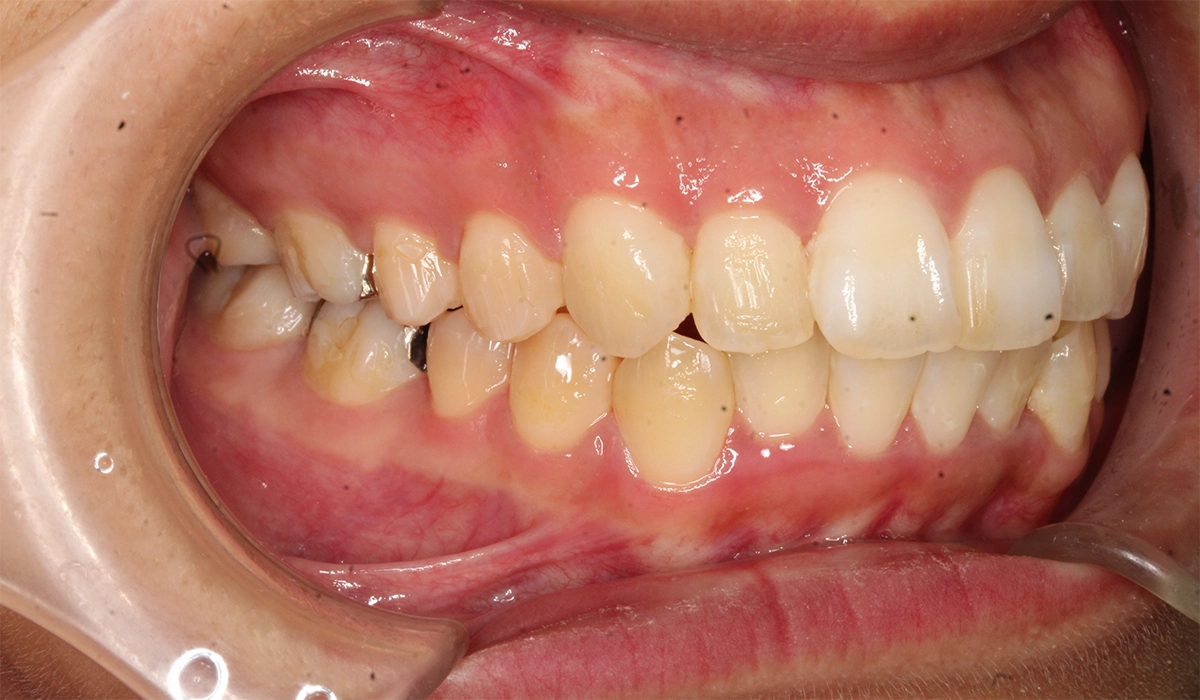

術前:左側

術後:左側